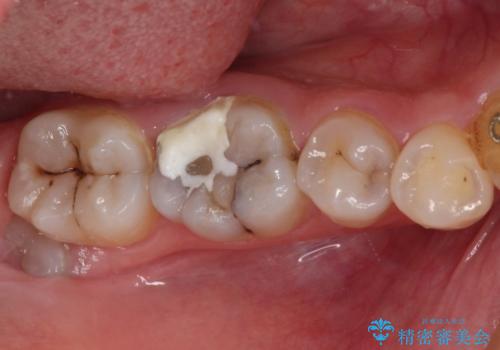

- 奥歯の虫歯を放置してしまい、痛みを感じることがあるとのことで来院された患者様です。

術前の診査では、神経を取り除かなくても済む可能性が示唆されましたが、実際に虫歯除去を進めたところ、レントゲン写真から読み取れる通り、神経組織にまで虫歯が及んでいることが分かりました。